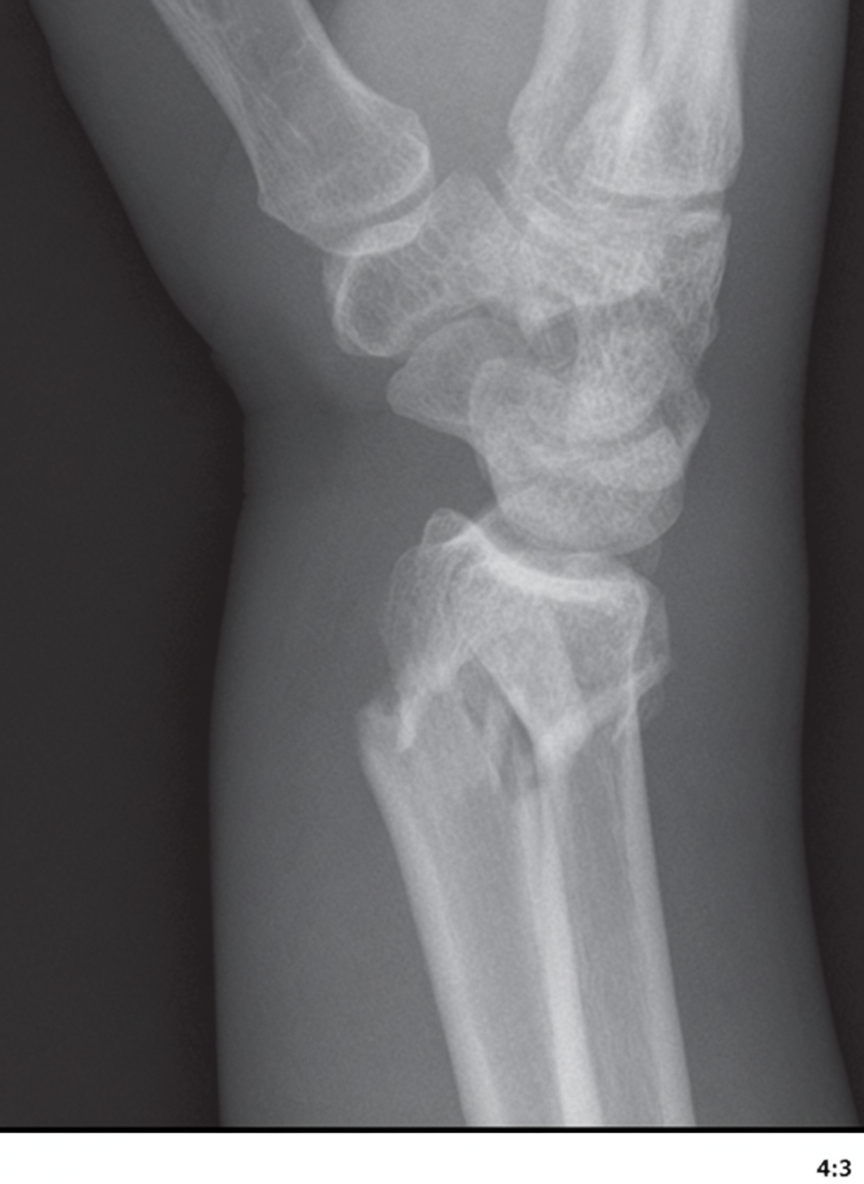

Which of the following complications occurs commonly in the fracture shown in the X-ray, EXCEPT?

Explanation: ***Delayed union*** - **Colles' fracture** involves the **metaphyseal region** of the distal radius, which has excellent **blood supply** and typically heals readily without delayed union. - The **cancellous bone** in this region promotes rapid healing, making delayed union an uncommon complication. *Malunion* - **Loss of reduction** is common due to **dorsal angulation** and **radial shortening** if immobilization is inadequate. - Results in **dinner fork deformity** and can cause functional impairment and cosmetic issues. *Shoulder stiffness* - Prolonged **immobilization** in a cast or sling commonly leads to **frozen shoulder** (adhesive capsulitis). - **Disuse** of the shoulder joint during healing period causes **capsular contracture** and reduced range of motion. *Carpal tunnel syndrome* - **Hematoma** and **swelling** at the fracture site can compress the **median nerve** in the carpal tunnel. - **Mal-reduction** with **volar angulation** can also narrow the carpal tunnel space, leading to nerve compression symptoms.